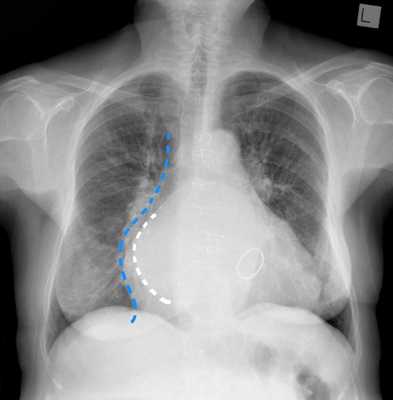

Об изменении конфигурации сердца за счет увеличения тех или иных его отделов также можно судить по результатам рентгенографии органов грудной клетки.

Зачастую об изменениях размеров сердца можно судить, выполнив обычную рентгенограмму грудной клетки в двух проекциях. Оценивая некоторые параметры (талия сердца, дуги сердца и др), рентгенолог может также заподозрить изменения конфигурации сердечных камер и их размеров.

Такой метод обследования, как рентгенография грудной клетки позволяет не только выявить застой крови в лёгких (а в тяжёлых случаях застойную пневмонию или отёк лёгких), но ещё и определить степень увеличения сердца. При митральных пороках с выраженным утолщением стенок левого предсердия сердце приобретает так называемую митральную конфигурацию - сглаживание талии сердца.

ГЛП на рентгенограмме